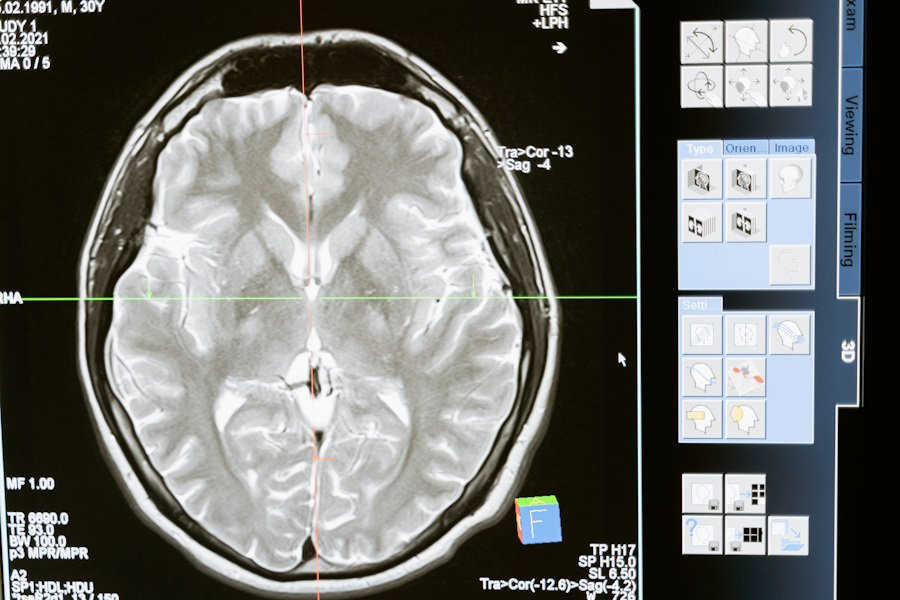

Головной мозг, наша самая сложная "компьютерная" система, подвержен воздействию многих факторов, и его работа остается загадкой. В нем содержится около 100 млрд нейронов, каждый из которых связан с другими посредством синапсов, создавая замысловатую паутину. Мозг способен выполнять операции со скоростью от 1012 до 1028 FLOPS/сек, в то время как самый быстрый суперкомпьютер 2022 года работает с мощностью 1,6 Х 1018 FLOPS/сек, сообщает ТАСС.

По данным неврологов, мозг чувствителен к воздействию различных факторов, включая алкоголь и курение, но наиболее вредными являются дефицит кислорода и глюкозы в крови. Нейроны в мозгу зависят от поступления глюкозы через кровь, и при отсутствии кровообращения они начинают умирать в течение пяти минут. Стресс также влияет на мозг, меняя химический баланс и передачу сигналов.